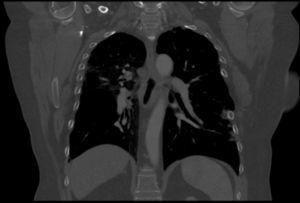

Pulmonary vein obstruction is usually an early complication, occurring during the first few hours after transplantation, and causes severe symptoms. Marked hypoxia, pulmonary edema, and pulmonary infiltrates are observed. If the lower lobe is more severely affected, a high suspicion for such a complication is warranted, and an early additional diagnostic test should be ordered. The initial test should be a transthoracic or transesophageal echocardiogram, in spite of this test being only useful for diagnosis when performed by an experienced operator, due to a challenging visualization and interpretation after recent surgery 6. Alternatively, chest CT angiography can be used, which also allows artery suture and distal vascularization to be assessed and reconstructions to be produced. CT angiography establishes the diagnosis in most cases. Anticoagulation using heparin and clinical course monitoring is used to manage partial thromboses and stenoses. In the event of a complete vein obstruction or a poor course, in patients with a very recent surgery, re-transplantation or lobectomy for double-lung transplantations, may be needed. If the patient is in a stable condition, several days have elapsed, and anatomic characteristics are favorable, an angioplasty with dilation and stent implant can be considered.

Arterial suture complications are usually less common and are found later. They result in persistent hypoxia and pulmonary hypertension. Diagnosis is based on CT angiography and/or arteriography. Some degree of arterial suture stenosis with no clinical significance is commonly found in CT angiography, due to donor-receptor size discordance or to the suture itself. Significant stenoses are due to kinking or thrombosis at the suture level. The former are usually treated win angioplasty and dilation, whereas usual therapy for the latter is stent implant if required. Anticoagulation is used for thrombotic cases 7.

Figure 3. Coronal view in CT angiography showing complete lower pulmonary vein obstruction after left lung transplantation.